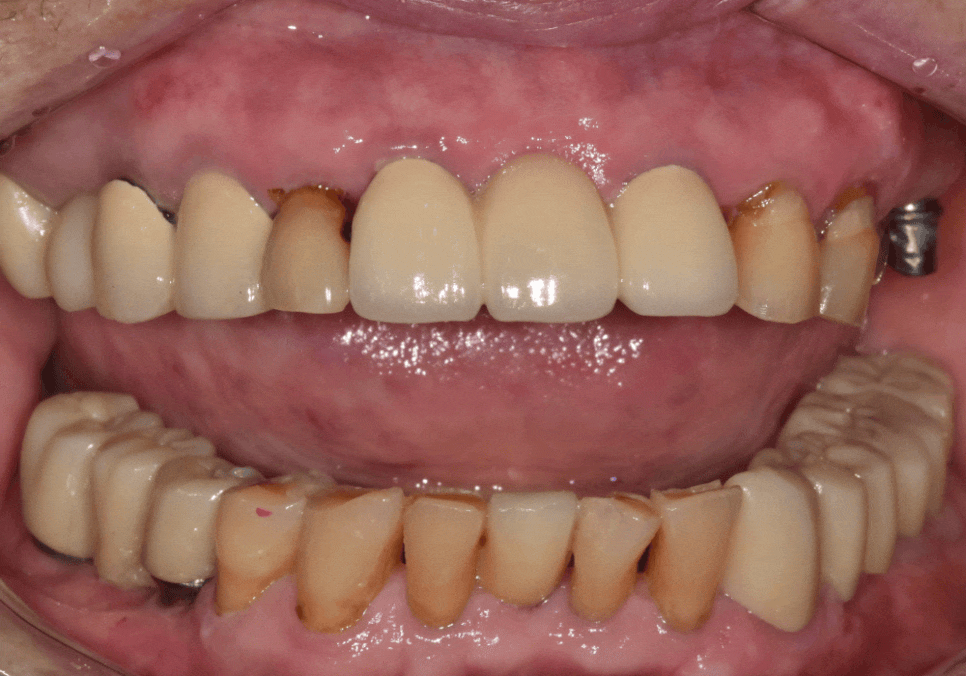

치유 기간을 거쳐

약 3개월 뒤

최종 보철까지 완성했습니다.

240709

231109 (전) 251108 (후)